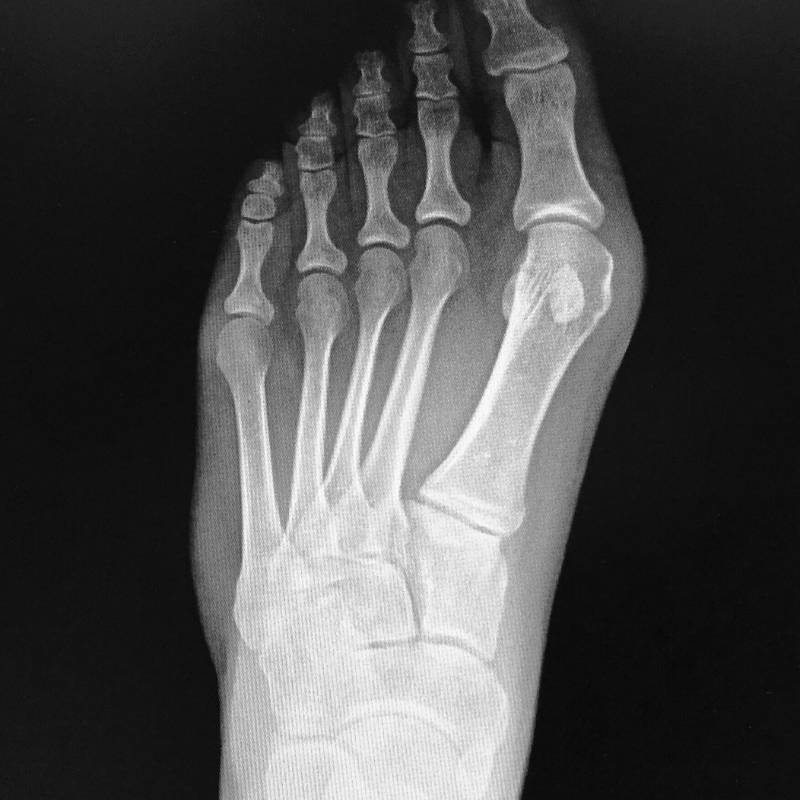

Digunakan untuk menilai struktur tulang kaki.

Pemeriksaan sinar-X pada tulang tumit untuk mengesan kecederaan.